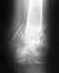

zdravstvuytetoto fakt 4to kost' vneshney lodyzhki sraslas' v polojenii kak by vnutr' to yest' verhniy oskolok smotrit 4ut' vnutr'imeyet li eto kakoye libo zna4eniye na amplitude dvijeniy?i yesli byli razryvy svyazok ili suhojiliya imeyet li eto silu pri razrabotke? tak kak prosess razrabotki idet medlenno...

Ну неужели непонятно, что описание рентгенограммы дилетантом не может быть основанием для каких-либо профессиональных советов? Покажите сам снимок.